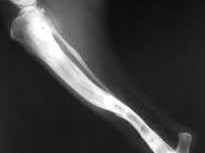

Página 2 de 3